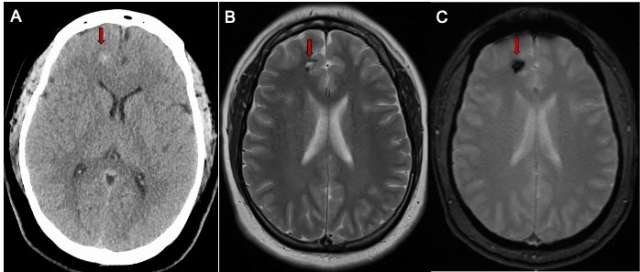

Whether the CCM has caused bleeding or not, the following advanced imaging (Figure 1) techniques may be used to diagnose it:

- Magnetic resonance imaging (MRI) scan can help locate the CCM and the area of affected brain or spinal cord.

- Computed tomography (CT) scan can assess any bleeding into the brain tissue.